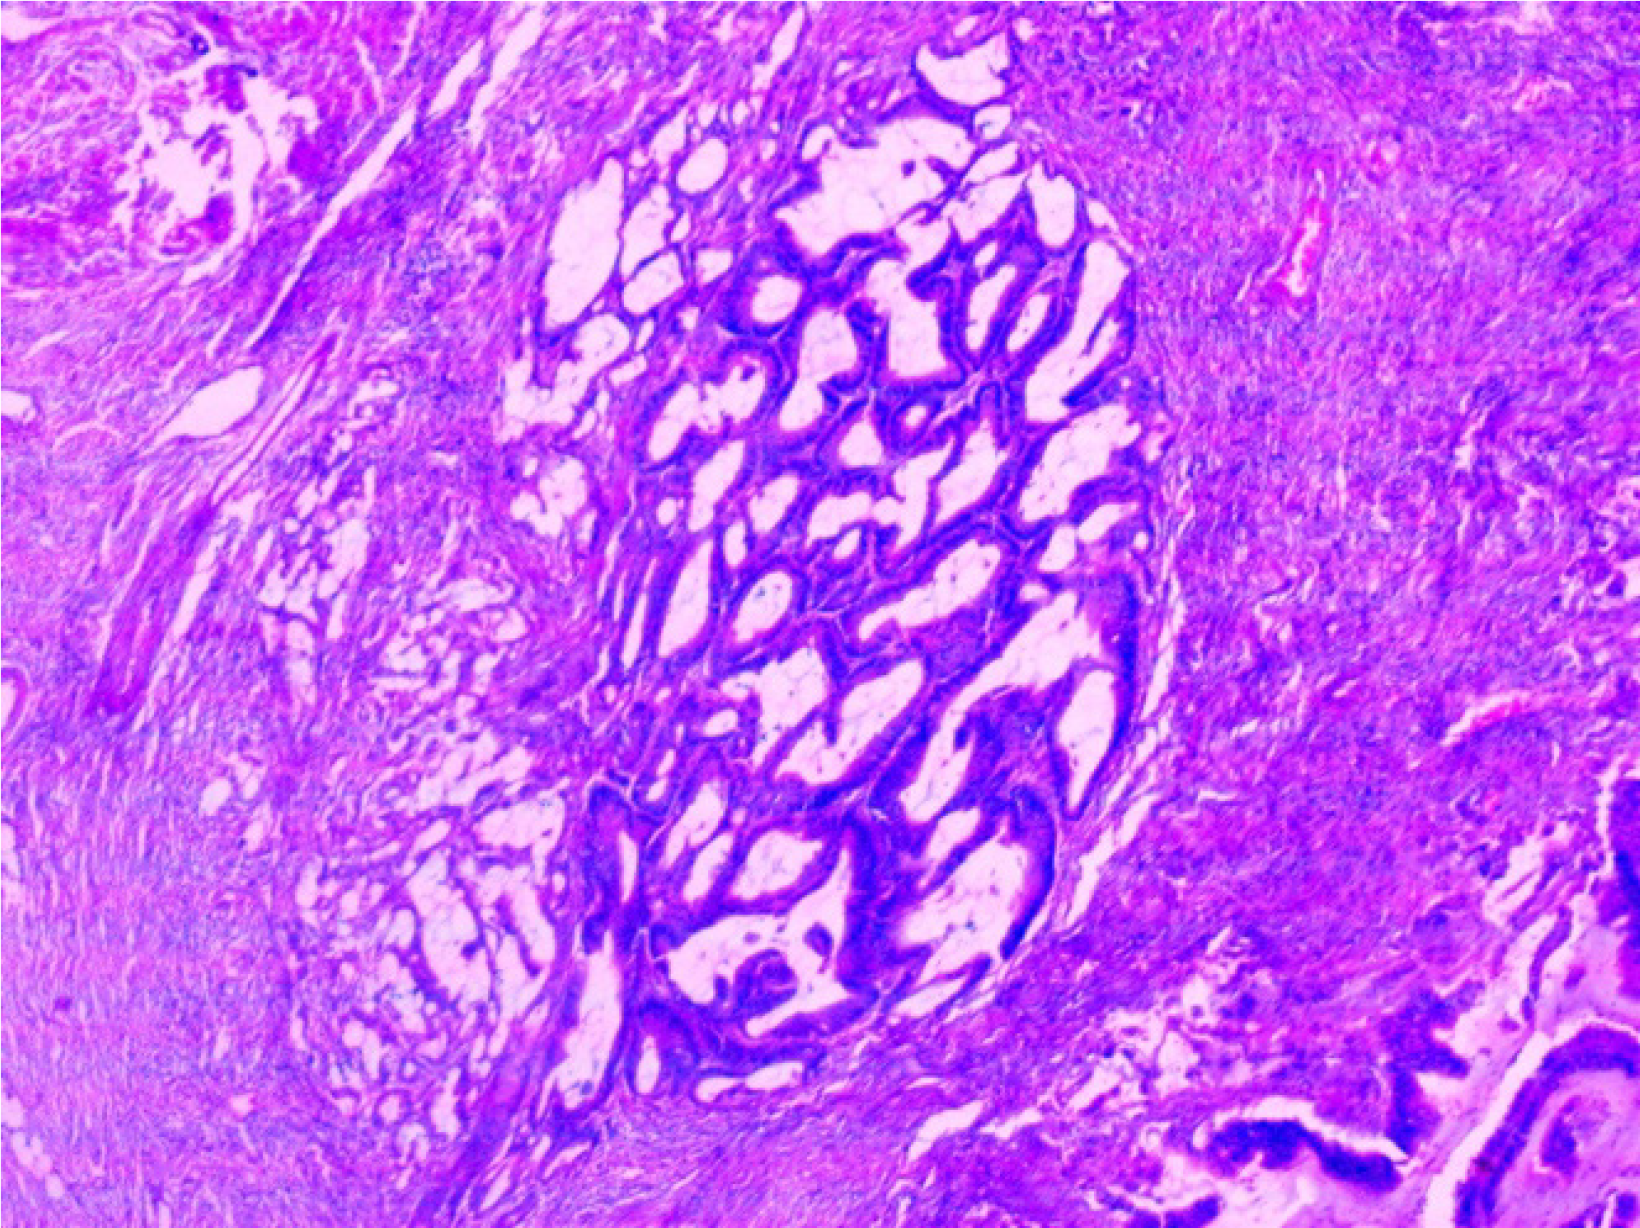

Figure 2

Histopathological micrograph showing polygonal cells with variable mucin and glandular debris invading the mucosa.